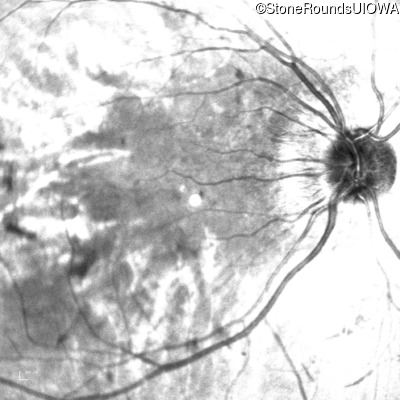

Infrared Fundus Photograph - Right - 20/200 -2

Exemplar